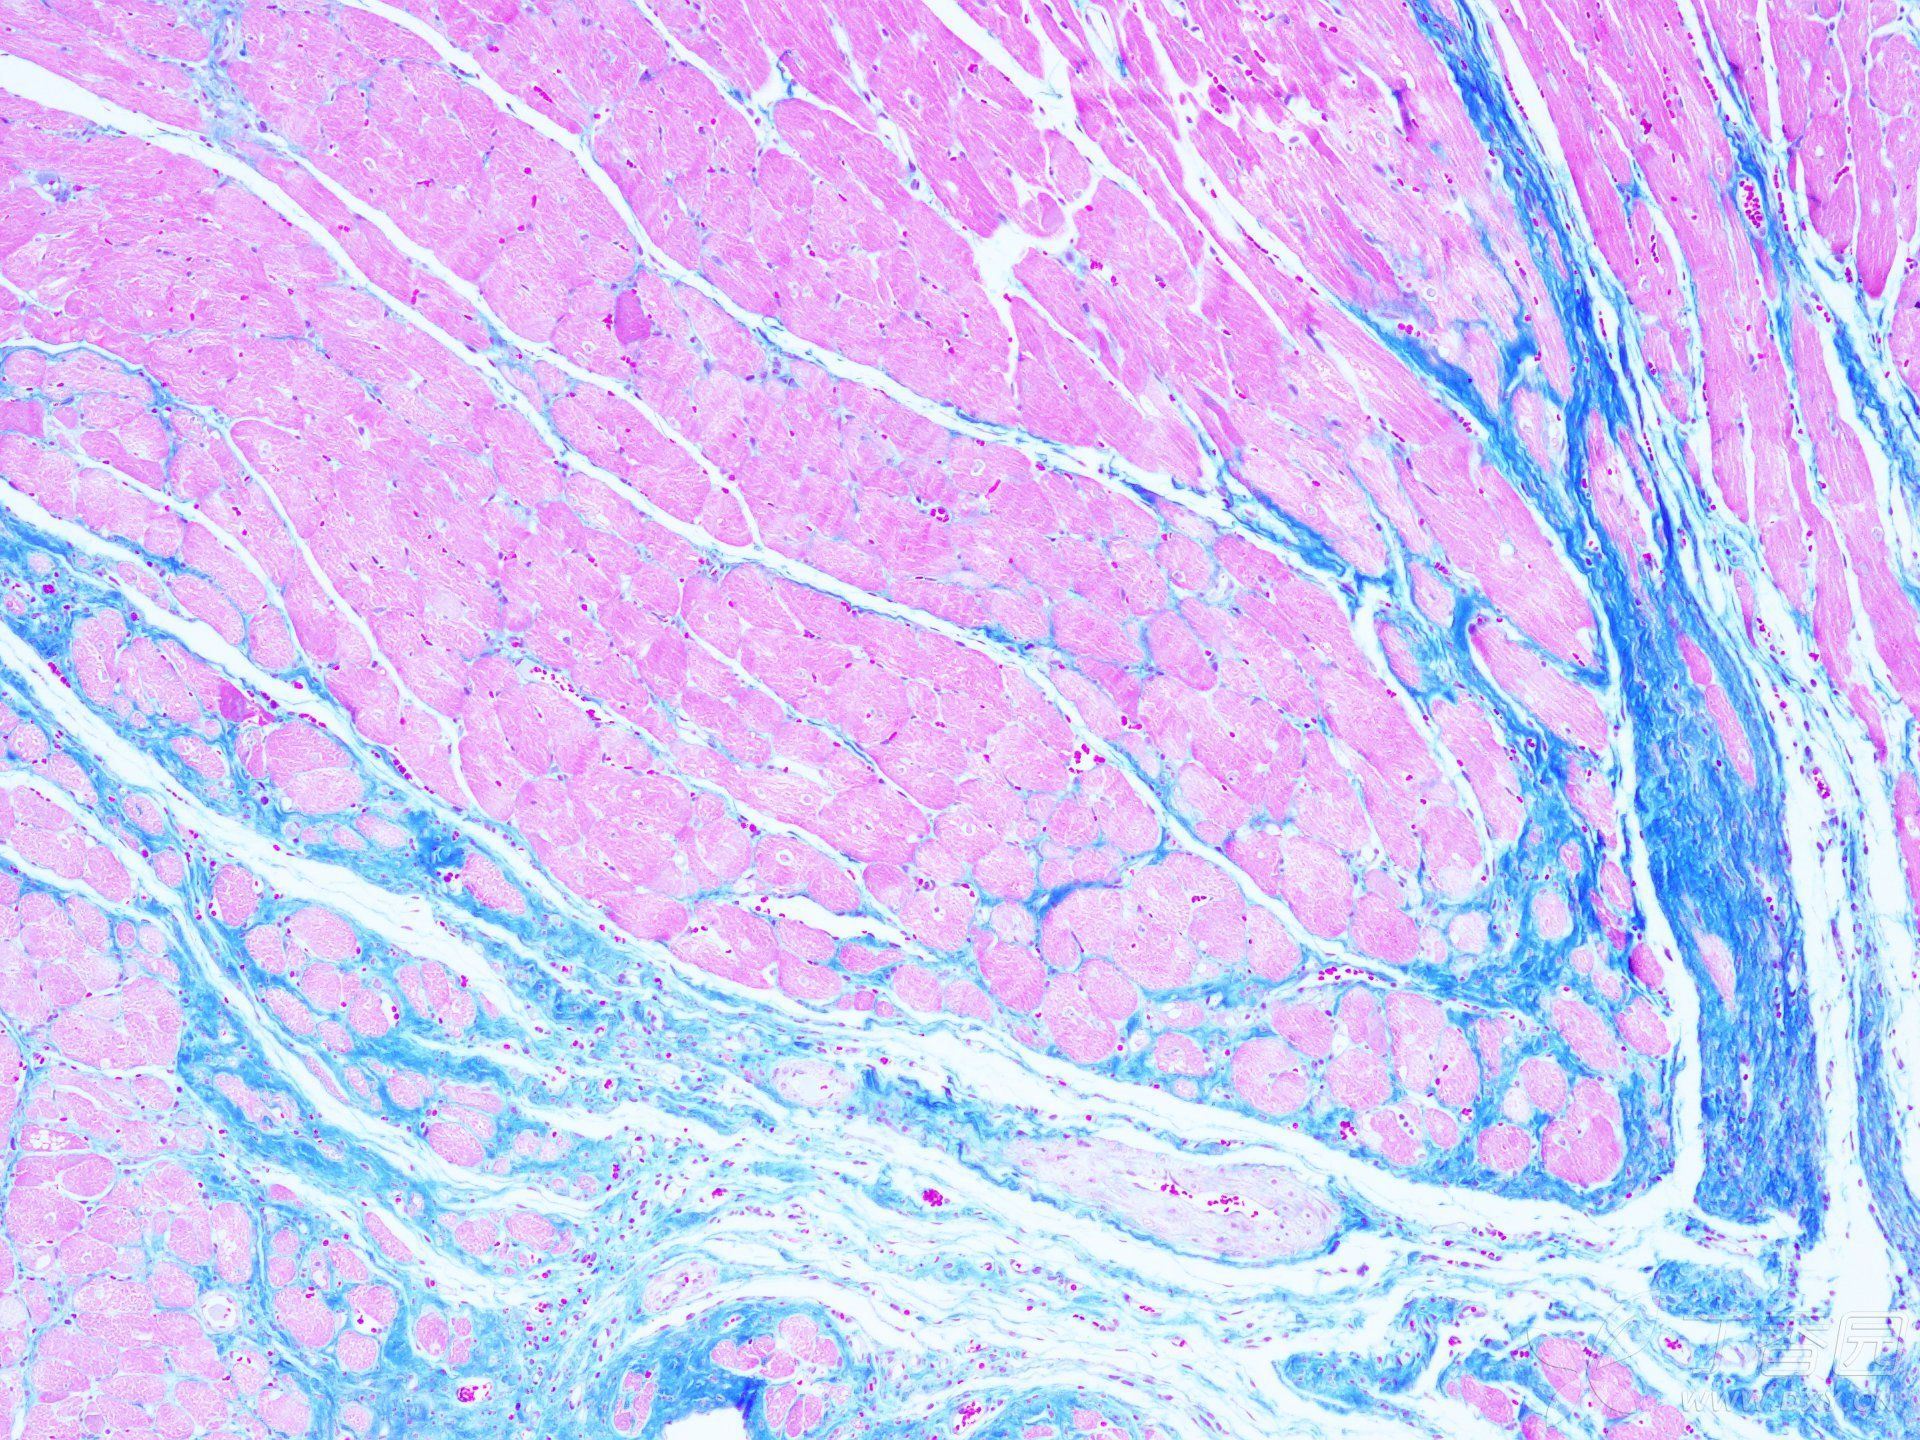

MASSON染色實(shí)驗(yàn)技術(shù)注意事項(xiàng)由普拉特澤生物為大家總結(jié)分享,普拉特澤生物病理染色實(shí)驗(yàn)平臺專業(yè)承接HE染色實(shí)驗(yàn)外包、油紅O染色等組織染色實(shí)驗(yàn)代做服務(wù),積累專業(yè)豐富的實(shí)驗(yàn)操作經(jīng)驗(yàn)。上次我們分享Masson染色實(shí)驗(yàn)報(bào)告分析不夠詳細(xì),有一些注意事項(xiàng)沒有寫出來,那今天咱們就為大家專門出一期詳細(xì)探討MASSON染色實(shí)驗(yàn)技術(shù)注意事項(xiàng),幫助大家更好的理解和應(yīng)用這個技術(shù),快點(diǎn)學(xué)起來吧!

MASSON染色作為一種重要的組織學(xué)染色方法,具有廣泛的應(yīng)用價值。然而,要想獲得準(zhǔn)確的染色結(jié)果,我們需要注意多方面的因素。從選擇合適的組織樣本、嚴(yán)格控制染色時間和溫度、注意染色劑的配制和保存,到細(xì)心觀察和處理染色結(jié)果,每一個環(huán)節(jié)都至關(guān)重要。